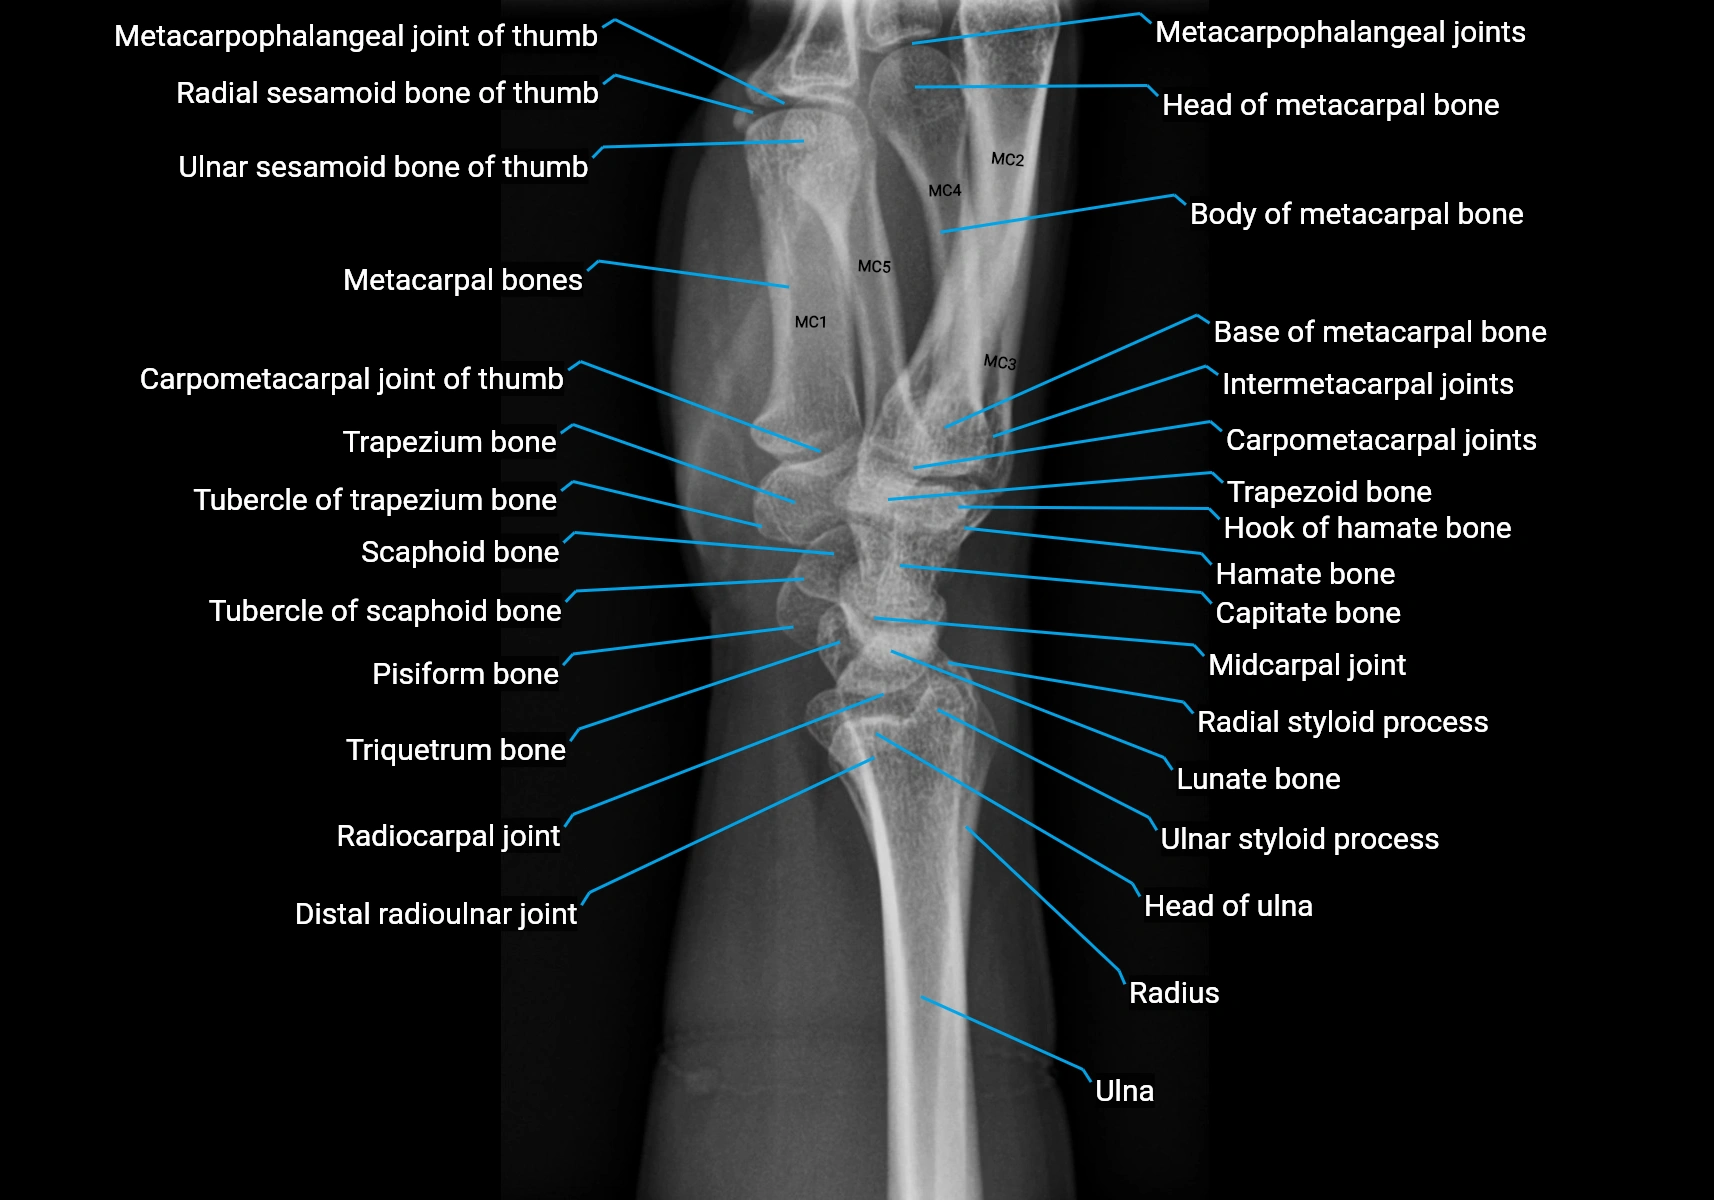

Origin: From the pisiform bone, the pisohamate ligament, and the tendon of the flexor carpi ulnaris.

Course: Muscle fibers run distally along the ulnar side of the hand, forming a flat tendon near the base of the little finger.

Insertion: Ulnar side of the base of the proximal phalanx of the fifth digit and the extensor expansion of the same finger.

• The tendon passes along the medial side of the fifth metacarpal and inserts into both the base of the proximal phalanx and dorsal digital expansion.